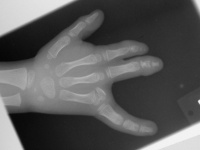

Congenital hand differences do not always fall into neat categories and a range of different approaches are usually possible. This boy's hand has a double level syndactyly between the index and middle finger - a bridge at the middle  phalanx level with an associated constriction ring groove, and a shallow web involving the same rays. There is also failure of separation of the ulnar hand parts with capitate-hamate coalition and absent ring ray other than  a partly separated metacarpal head.

The procedures were staged. In the first procedure, the constriction ring syndactyly was taken down by splitting the skin bridge into dorsal and palmar  skin flaps. This removed the angular tethering force on the index finger and allowed maturation before the second procedures.

First stage complete.